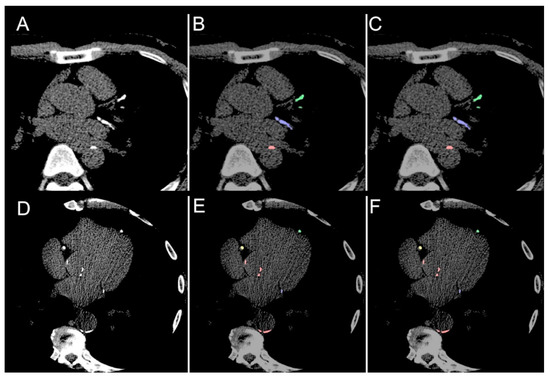

| Total coronary (LAD + RCA + LCx) | Overall | 0.952 | (0.921, 0.981) | - |

| Male | 0.948 | (0.920, 0.981) | 0.350 | |

| Female | 0.965 | (0.933, 0.980) | ||

| Age < 65 years | 0.950 | (0.913, 0.981) | 0.742 | |

| Age ≥ 65 years | 0.957 | (0.930, 0.977) | ||

| LAD | Overall | 0.971 | (0.930, 1.000) | - |

| Male | 0.963 | (0.919, 1.000) | 0.058 | |

| Female | 0.988 | (0.968, 1.000) | ||

| Age < 65 years | 0.970 | (0.941, 0.999) | 0.980 | |

| Age ≥ 65 years | 0.975 | (0.911, 1.000) | ||

| RCA | Overall | 0.963 | (0.889, 0.991) | - |

| Male | 0.951 | (0.880, 1.000) | 0.633 | |

| Female | 0.977 | (0.923, 0.991) | ||

| Age < 65 years | 0.964 | (0.874, 0.999) | 0.875 | |

| Age ≥ 65 years | 0.959 | (0.899, 0.987) | ||

| LCx | Overall | 0.955 | (0.894, 1.000) | - |

| Male | 0.954 | (0.887, 1.000) | 0.388 | |

| Female | 0.958 | (0.942, 0.998) | ||

| Age < 65 years | 0.954 | (0.905, 0.999) | 0.897 | |

| Age ≥ 65 years | 0.955 | (0.887, 1.000) | ||

| Aortic | Overall | 0.832 | (0.759, 0.897) | |

| Male | 0.802 | (0.760, 0.905) | 0.996 | |

| Female | 0.834 | (0.764, 0.883) | ||

| Age < 65 years | 0.833 | (0.776, 0.933) | 0.204 | |

| Age ≥ 65 years | 0.793 | (0.756, 0.862) | ||